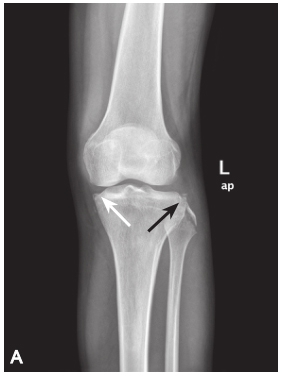

A. 膝关节 X 线前后位片。白色箭头示反 Segond 骨折。黑色箭头显示胫骨平台外侧及腓骨头骨折。B. 膝关节 MRI。矢状位 PDWI:ACL 和 PCL 损伤后胫骨水肿;C. 冠状位 T2WI:胫骨平台内侧撕脱性骨折(反 Segond 骨折)和胫骨平台外侧撕脱骨折